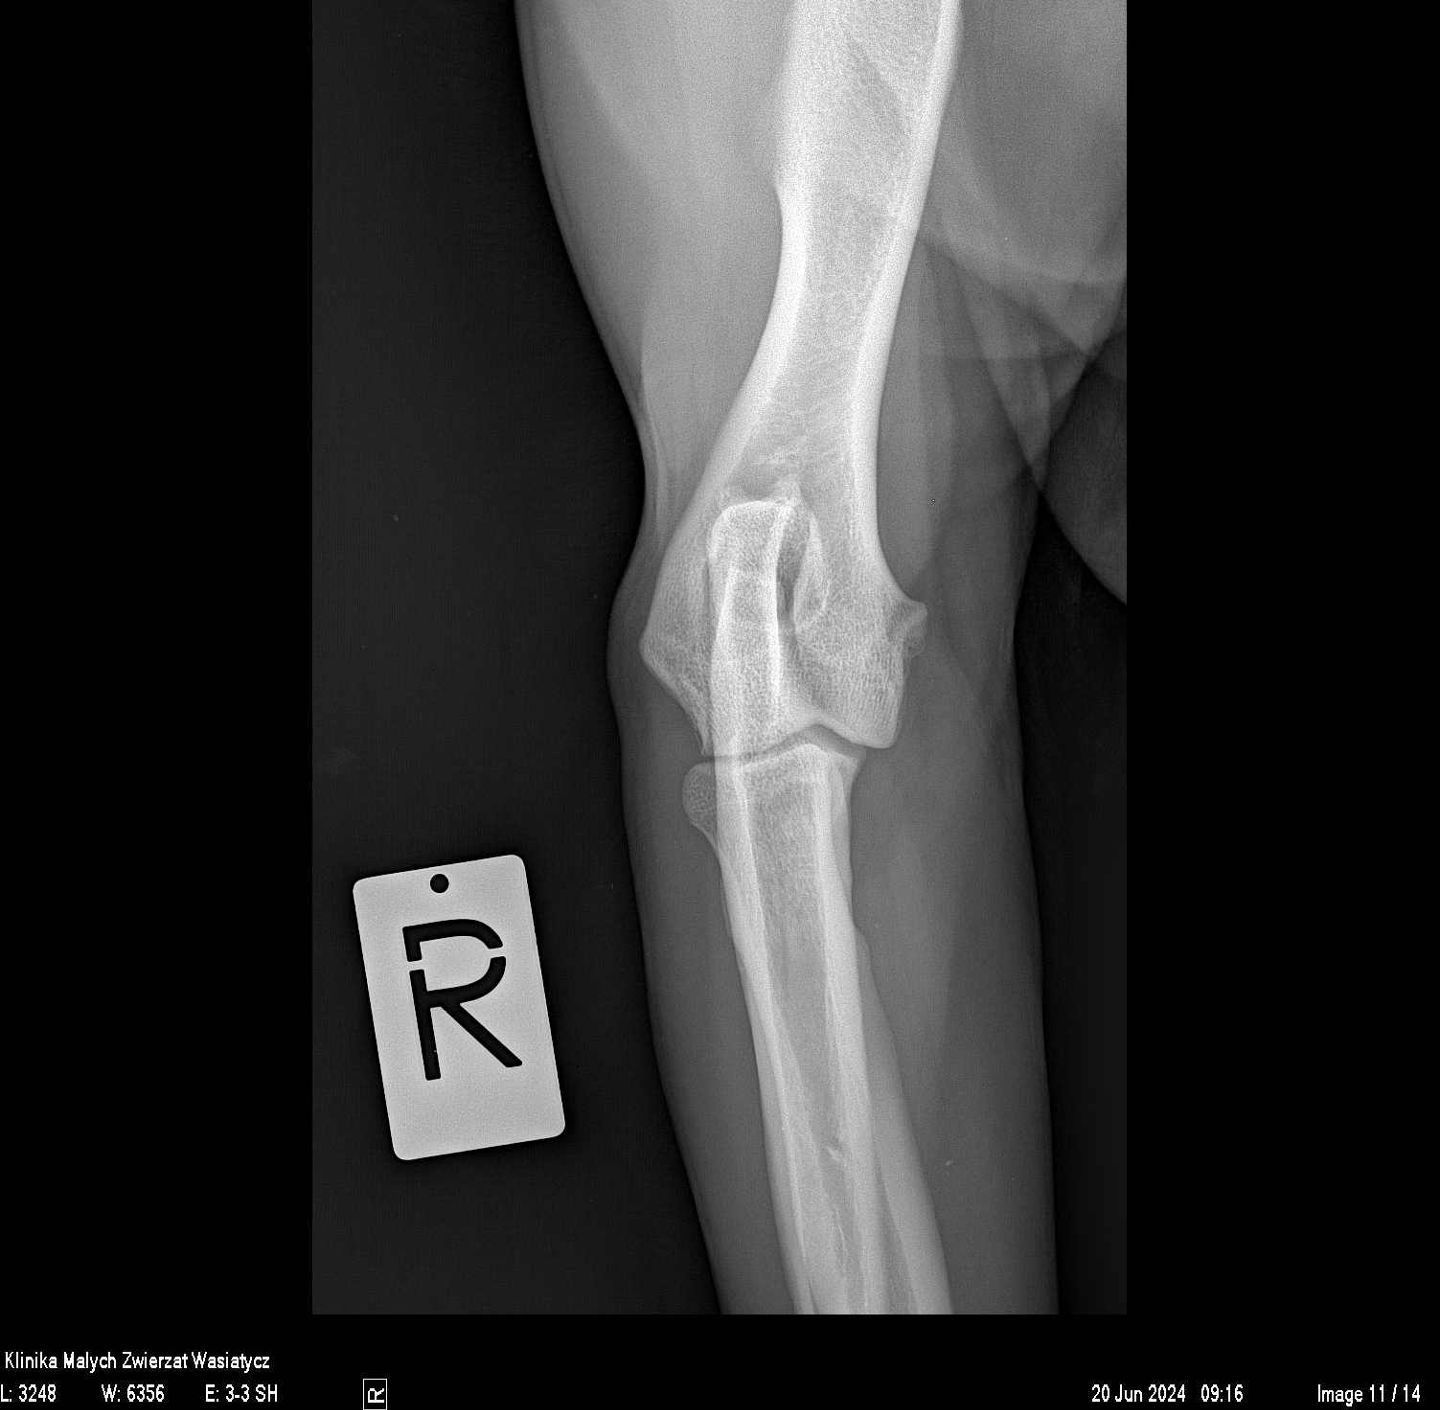

W naszej klinice pracownia rentgenowska stanowiła zawsze bardzo ważne miejsce diagnostyczne. Jako placówka specjalizująca się w ortopedii staramy się zapewnić najwyższą jakość zdjęć rtg, zarówno w zakresie dokładności ułożeń jak i parametrów ekspozycji.

Obecnie, w naszej pracy wykorzystujemy najwyższej klasy sprzęt rentgenowski hiszpańskiej firmy Initech, który został specjalnie skonfigurowany zgodnie z naszymi potrzebami. Jest to również system radiologii bezpośredniej.

Rocznie w naszej klinice wykonywanych jest prawie 20 000 zdjęć rentgenowskich. Każde z nich jest wykonywane przez stale doskonalących się specjalistów, analizowane przez wysokiej klasy lekarzy weterynarii, w tym również specjalistów radiologów. Wszystko to sprawia, że badanie rtg dostarcza maksymalną ilość informacji, która potrzebna jest w procesie diagnostycznym.